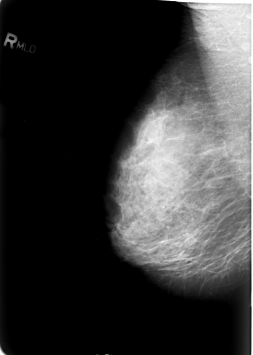

B_3029_1.RIGHT_CC

RIGHT_CC LINES 5568 PIXELS_PER_LINE 3944 BITS_PER_PIXEL 12 RESOLUTION 50 NON_OVERLAY

RIGHT_MLO LINES 5680 PIXELS_PER_LINE 4040 BITS_PER_PIXEL 12 RESOLUTION 50 NON_OVERLAY